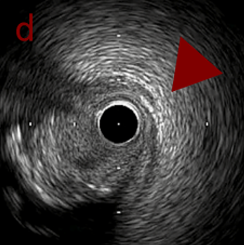

IVUS after OAS high speed 3回追加

IVUS imaging after high speed 3回追加

a,b,cの十分な石灰化のsanding。

High riskのbias所見へと変わっていったdの部位に関してはpinpoint OASを行うことでinjuryなく治療できた。